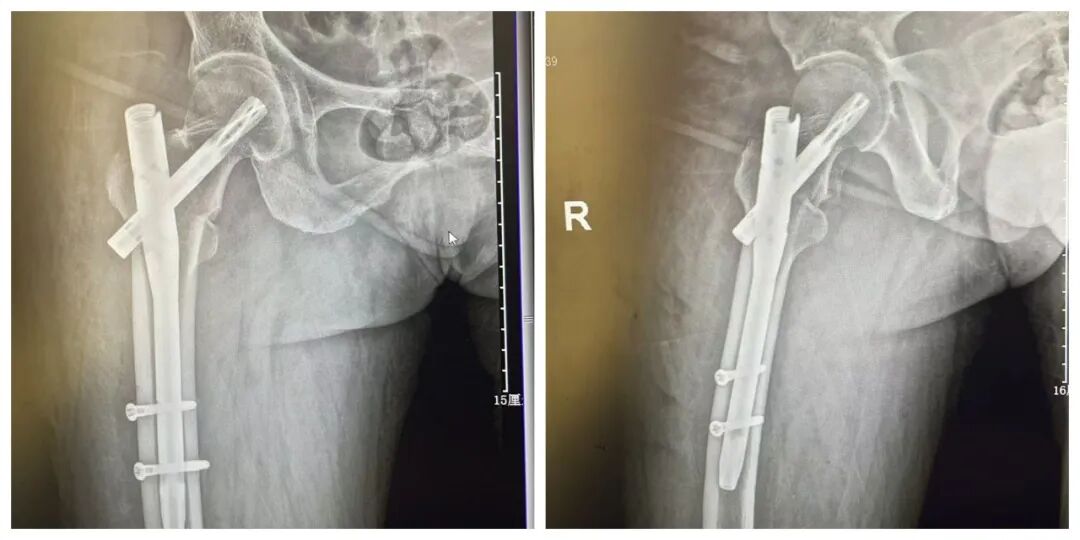

患者术后影像